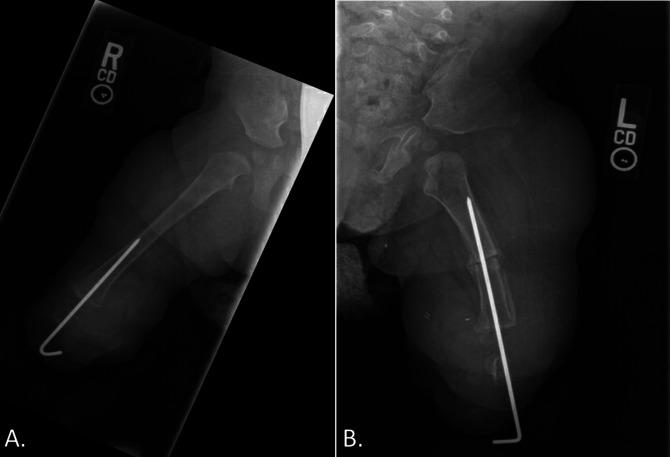

Tibial deficiency (also known as tibial hemimelia) is a rare condition with variable presentation. A 2-month-old patient presented with absent bilateral tibias. When the patient was 1 year, a novel reconstructive surgery was done. A bilateral fibular resection with pedicled calcaneus transfer was done, allowing for transfer of the calcaneus along with the overlying glabrous skin and soft tissues to the end of the femur. The patient was permitted to weight-bear after the 4-week postoperative follow-up. At the six-month follow-up, the patient was able to pull to stand and walk with assistance without any reports of pain.

胫骨发育不全(也称为胫骨半肢畸形)是一种罕见的疾病,表现多样。一名 2 个月大的患儿双侧胫骨缺失。患儿 1 岁时,接受了一种新的重建手术。进行了双侧腓骨切除和带蒂跟骨转移,将跟骨连同其上方的无毛皮肤和软组织转移到股骨末端。术后 4 周随访时,患儿开始负重。在 6 个月的随访中,患儿能够在辅助下拉站和行走,没有任何疼痛报告。